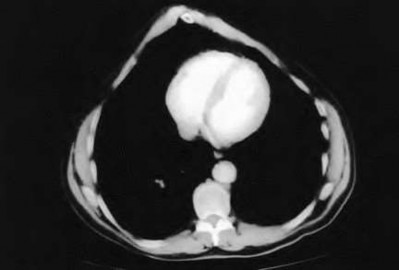

A 20-year-old park ranger trips and falls onto his right wrist with the wrist in extension and pronation. The local urgent care orders both radiographs and a CT, which you review and determine to be normal. The patient complains of ulnar-sided wrist pain. On exam, his tenderness is localized to the fovea. Ulnar deviation also causes him pain. There is no snapping sensation with wrist supination, flexion, and ulnar deviation. He otherwise has 5/5 strength to his first dorsal interosseous muscle with 4mm static two-point discrimination on the ulnar side of the 4th digit. Which of the following injuries is most likely responsible for his symptoms and exam?